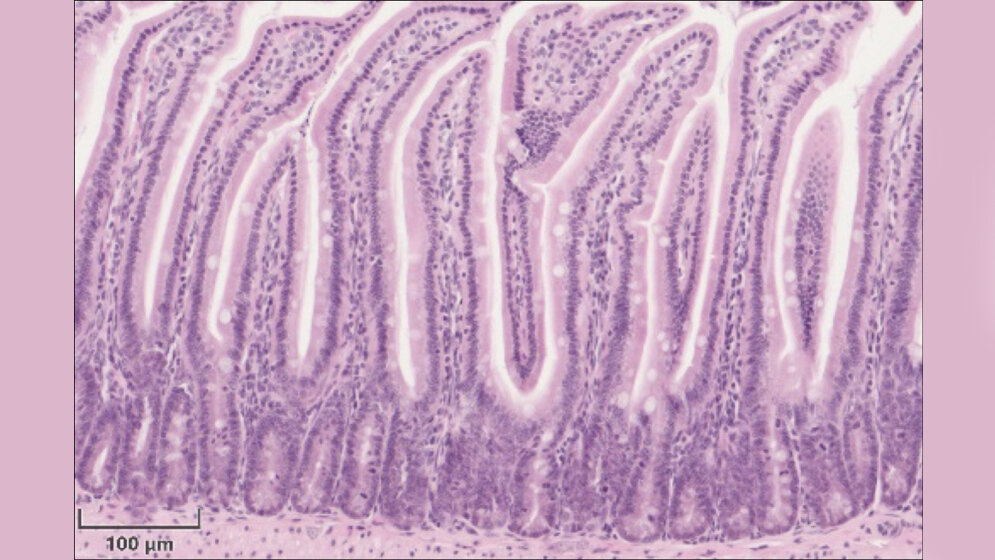

Stammzellen sind für den Erhalt und die Regeneration von Geweben unerlässlich. Die Stammzellen im Darm sind umgeben von so genannten Paneth-Zellen. Diese sind für die lokale Immunabwehr verantwortlich und sorgen für eine Umgebung, in der es den Stammzellen gut geht und damit für deren Erhalt.

Personen, die an Morbus Crohn leiden, haben insgesamt weniger Paneth-Zellen, die noch dazu in ihrer Funktion eingeschränkt sind. Die Forschungsgruppe beschäftigte sich mit den Fragen, was die Veränderungen der Paneth-Zellen verursacht und inwieweit der Zellstoffwechsel in den Stammzellen eine Rolle spielt.

Dazu wurde neben Studien an Mäusen auch Darmgewebe von Patientinnen und Patienten mit Morbus Crohn, das operativ entfernt wurde, analysiert und genauestens kartiert. Nach sechs Monaten haben die Wissenschaftlerinnen und Wissenschaftler den Darm der Patienten erneut endoskopisch begutachtet und nach Entzündungsanzeichen gesucht.

Mikroskopische Veränderungen der Stammzellen waren in der Studie besonders häufig bei Patientinnen und Patienten zu finden, die nach sechs Monaten wieder Entzündungsanzeichen im Darm zeigten. „Das Erscheinungsbild der Stammzellen ist ein sehr frühes Anzeichen für den Beginn entzündlicher Prozesse und eignet sich, um die Wahrscheinlichkeit des Wiederaufflammens der Darmentzündung nach einer teilweisen Entfernung der betroffenen Dünndarmabschnitte abzuschätzen. Hier wäre ein geeigneter Ansatzpunkt für eine therapeutische Intervention“, erklärt Dirk Haller, Professor für Ernährung und Immunologie an der TUM.